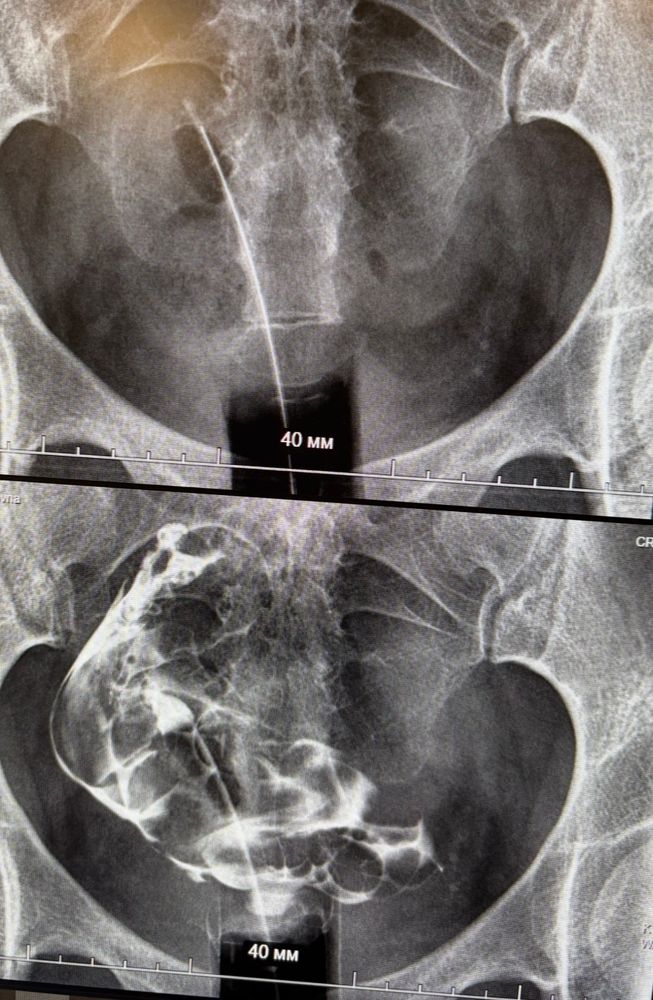

Однорогая матка по гсг и гистере

Матка сильно смещена. Это вообще бывает, у кого с такой патологией получилось? Я в эко. На гистере сказали матка норм размеров хотя бы.